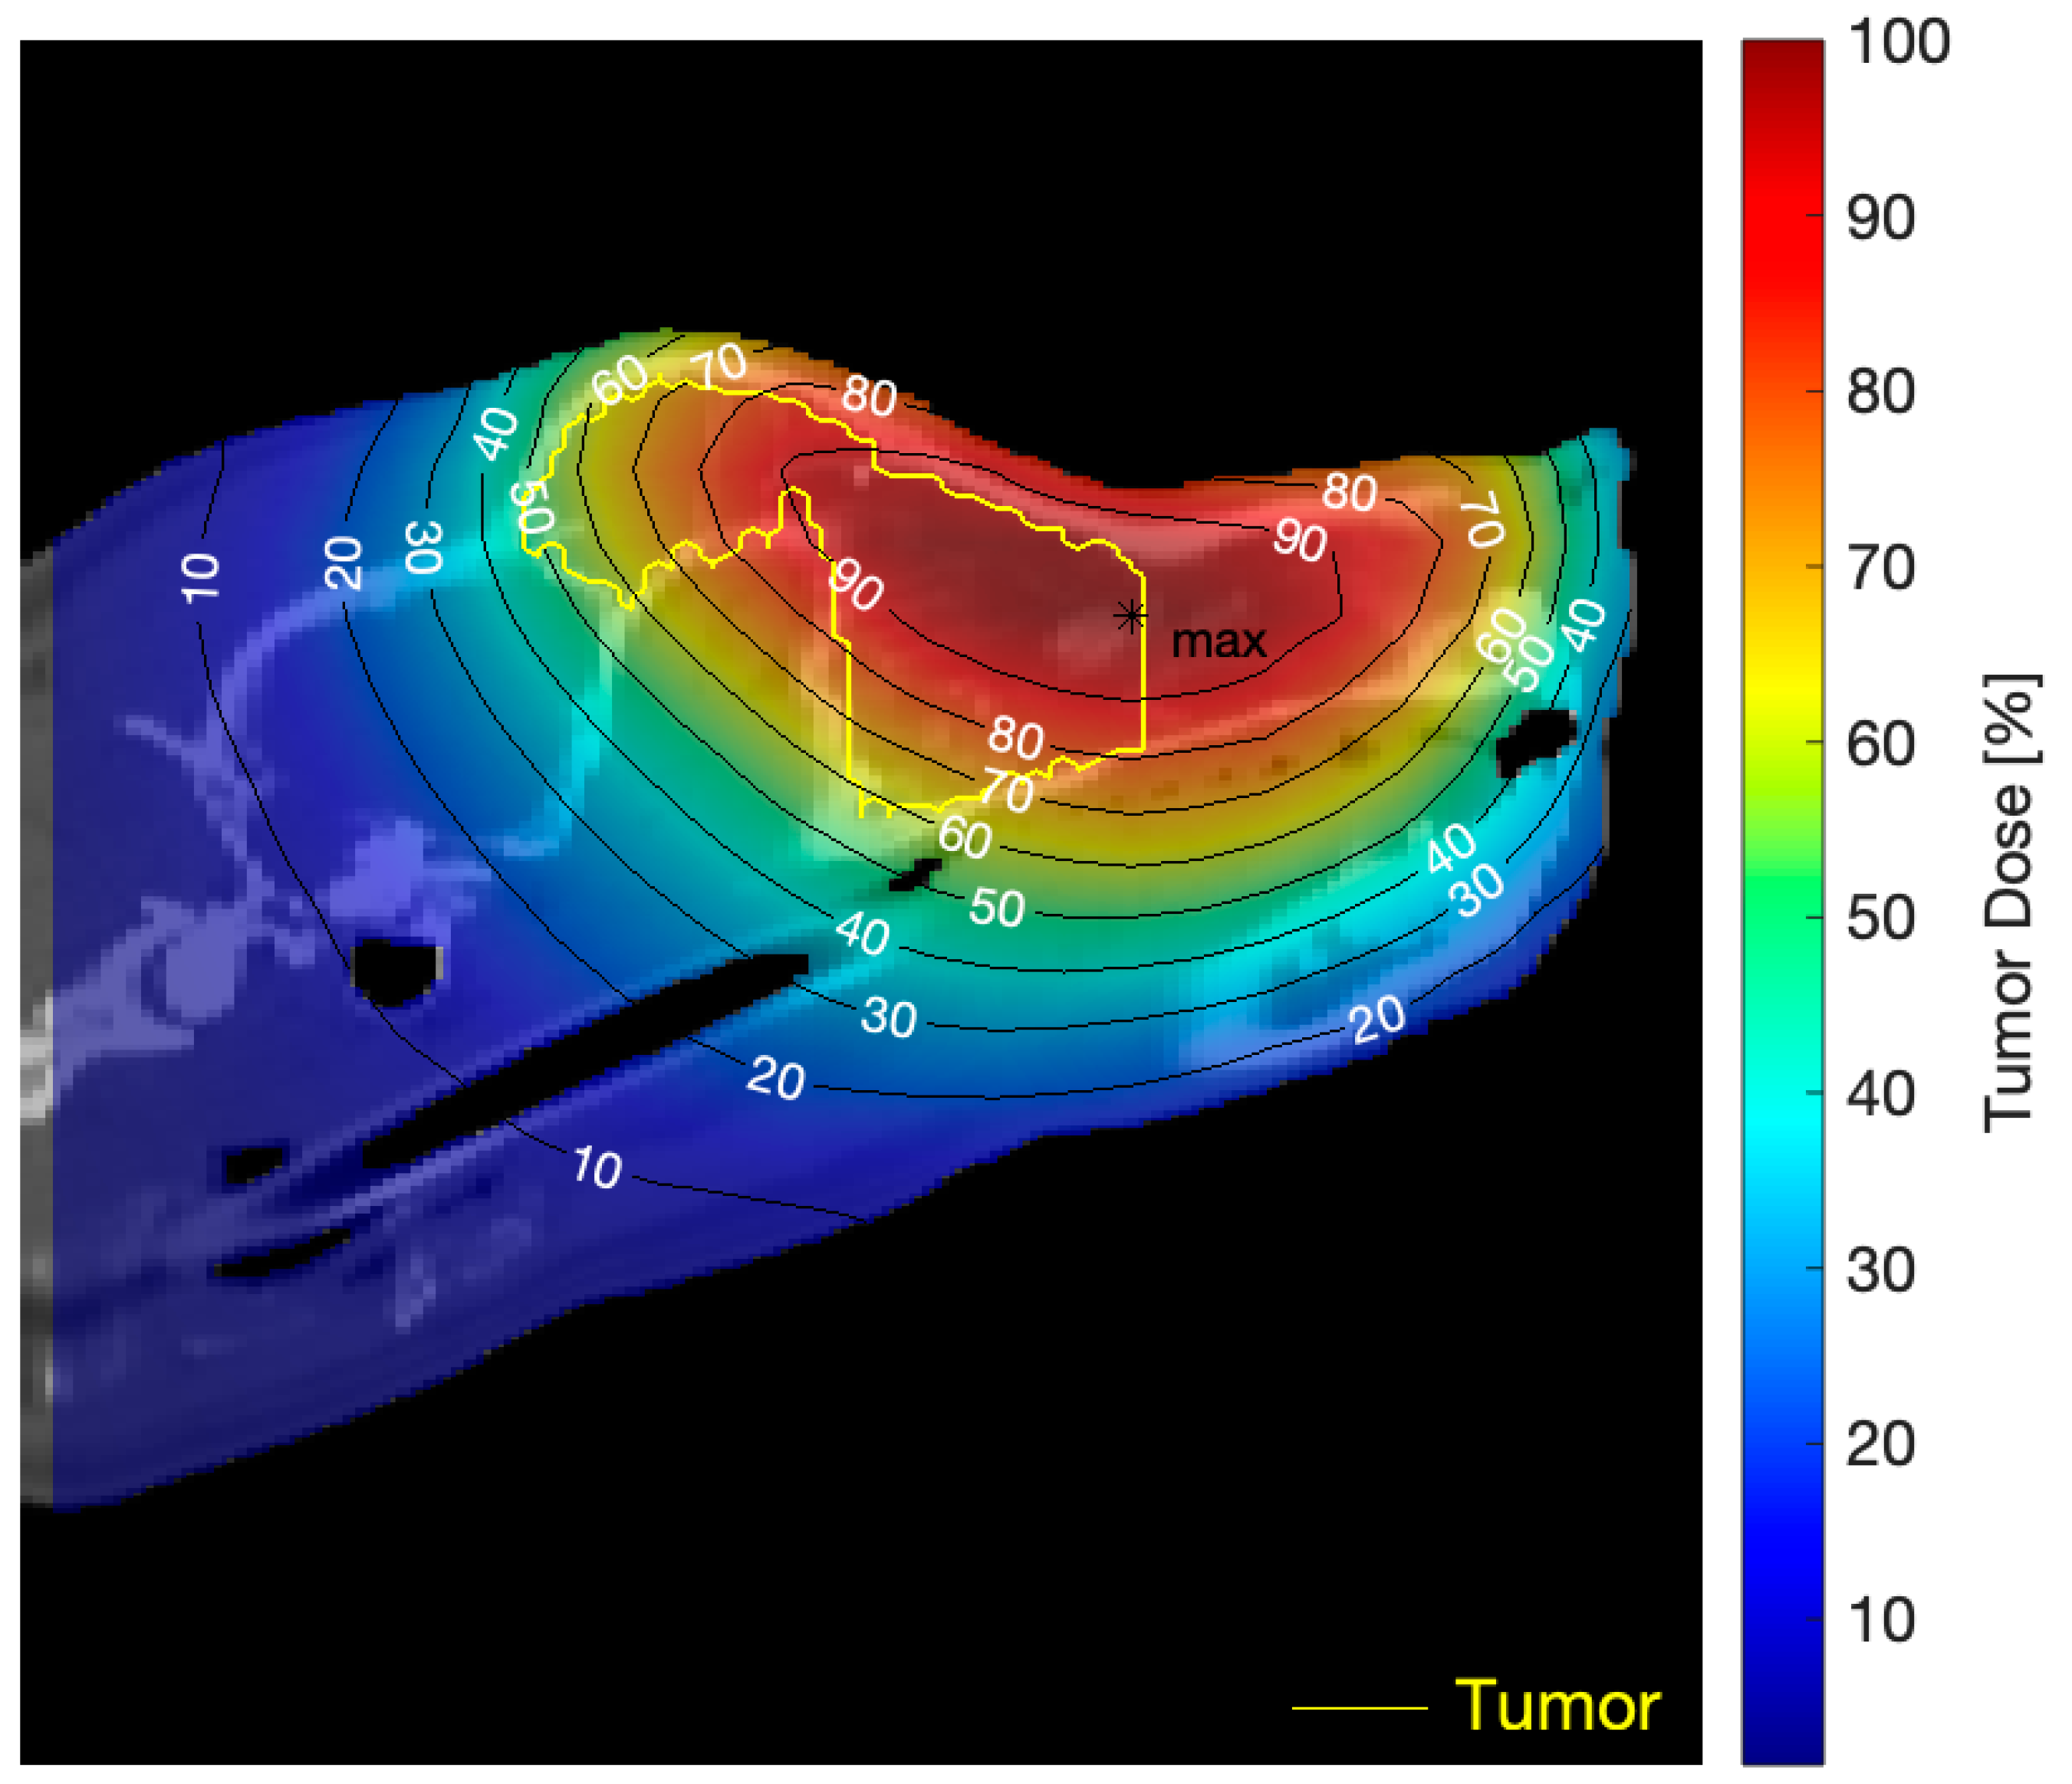

| Mora I | BNCT1 | 11 (7, 14) | 28 (17, 37) |

| BNCT2 | 3 (2, 4) | 8 (4, 10) | |

| Jake | BNCT1 | 10 (7, 11) | 26 (18, 31) |

| BNCT2 | 10 (7, 11) | 26 (18, 31) | |

| Mora I | BNCT1 | 4.5 (3.2, 5.5) | 9.4 (7.9, 10.4) | 6.0 (3.8, 8.2) | 6.8 (0.7, 17.6) | 9.3 |

| BNCT2 | 1.5 (1.1, 1.8) | 2.7 (2.3, 3.2) | 1.9 (1.2, 2.7) | 1.9 (0.2, 5.1) | 2.6 | |

| Jake | BNCT1 | 4.3 (3.1, 5.7) | 4.0 (3.0, 5.4) | 1.5 (0.7, 4.0) | 3.4 (0.4, 15.3) | 7.7 |

| BNCT2 | 4.3 (3.1, 5.7) | 4.0 (3.0, 5.4) | 1.5 (0.7, 4.0) | 3.4 (0.4, 15.3) | 7.7 | |

| Labrador Mora I 9 years old | Oral amelanotic melanoma TV: 342 cm3 | 5 surgeries Immuno-therapy pre-BNCT | 2 appl., 5 weeks apart; 2 portals/appl. | PR TV 1 month post 1st appl.: 284 cm3 TV 2.5 months post 1st appl.: 149 cm3 Cause of death: Euthanasia due to lung metastasis diagnosed 2 months post BNCT Survival post 1st appl.: 2.5 months | Moderate mucositis | Positive tumor response and clinical benefit |

| Labrador Jake 12 years old | Nasal SCC (poorly differentiated) Myasthenia TV: 29 cm3 | 1 surgery pre-BNCT Palliative chemo-therapy 7 months post BNCT, after regrowth | 2 appl., 4.5 weeks apart; 2 portals per appl. | PR as revealed by complete reduction in visible tumor volume and improvement in quality of life Cause of death: euthanasia due to recurrence and decline No CT scan 1 month post treatment Survival: 8.5 months post-BNCT | Moderate–severe mucositis that responded to medication | Positive tumor response and clinical benefit |